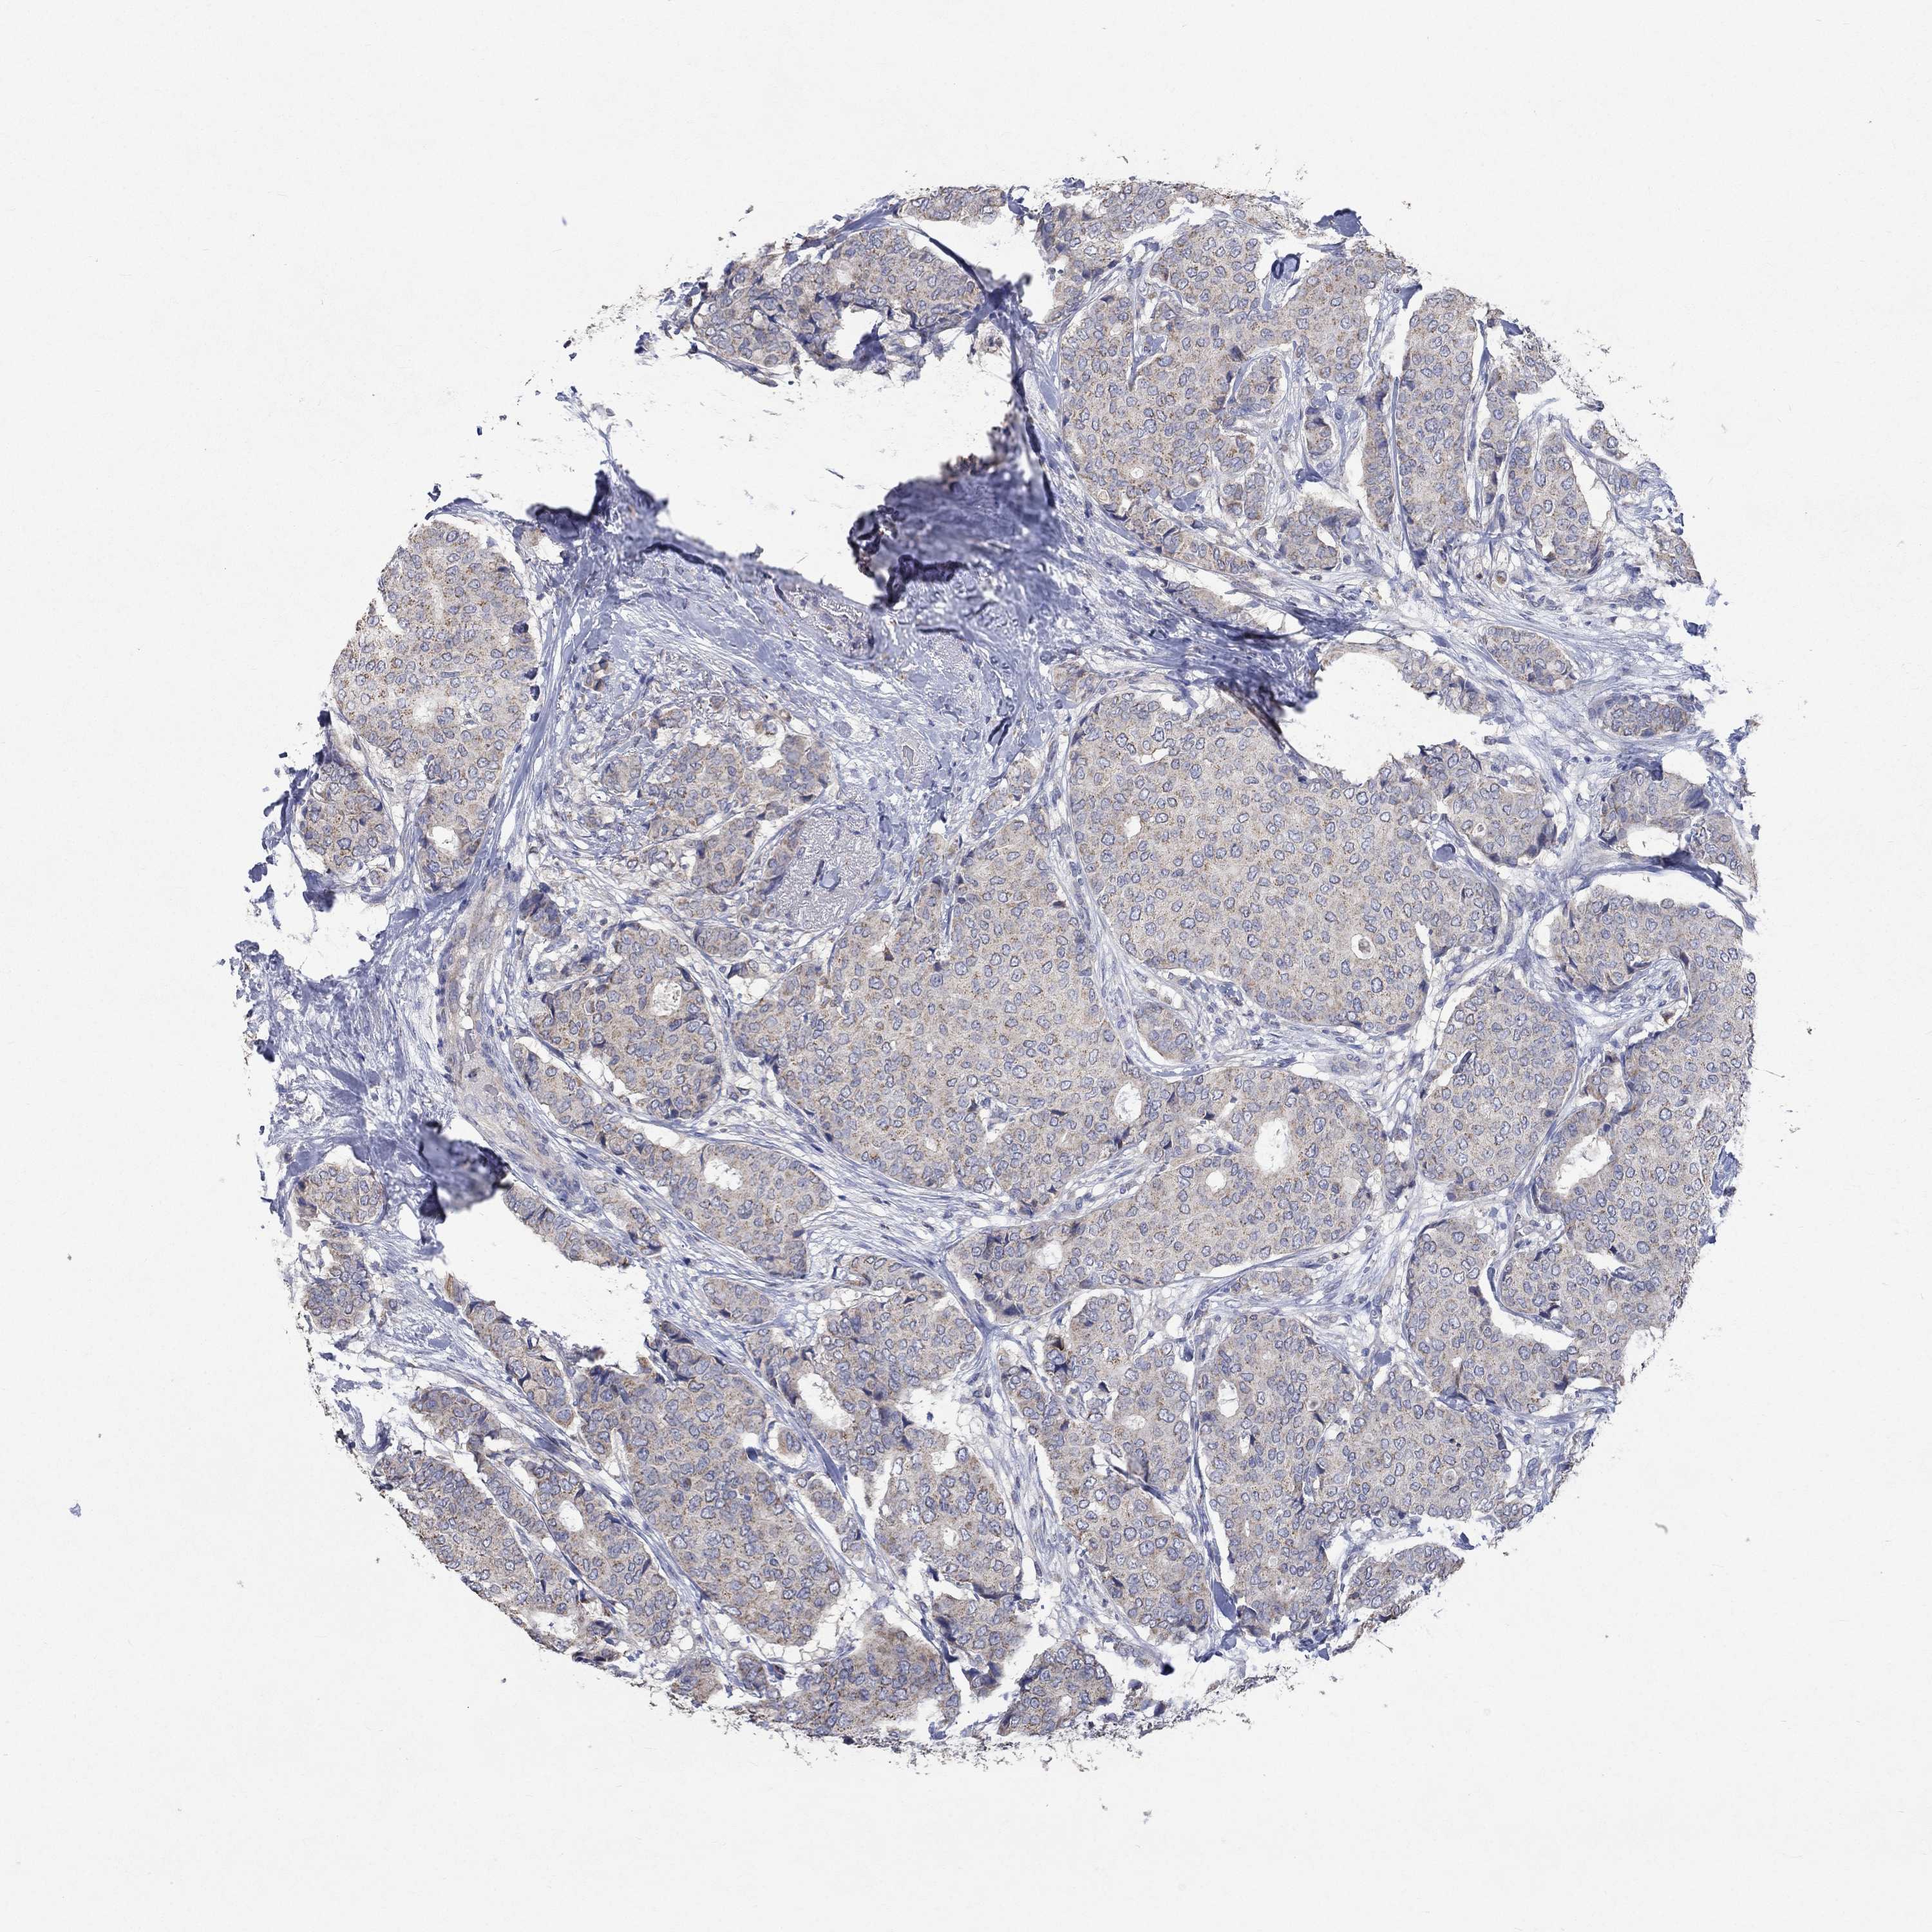

CANCER BREAST CANCER Show tissue menu

BRCA TCGA BRCA VALIDATION PROTEIN EXPRESSION

ANTIBODIES

AND

VALIDATION